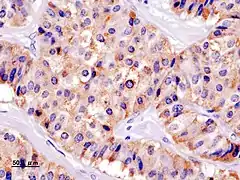

_Chromogranin_A.JPG.webp)

Окраска инсулиномы Chromogranin A

Histopathology of pancreatic endocrine tumor (insulinoma). Insulin immunostain.